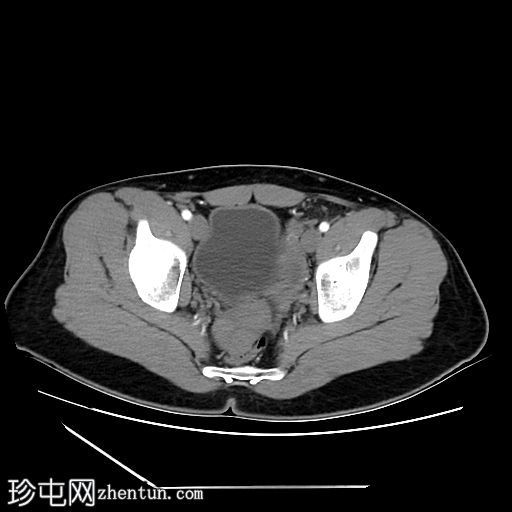

轴位增强扫描

门静脉期

5.jpg

盆腔左侧可见一形态良好的子宫样结构(57 x 17毫米),开口于前列腺尿道。

右侧睾丸位于盆腔右侧,膀胱与直肠之间。大小:56 x 29 毫米。

左侧睾丸位于盆腔中线左侧,膀胱上方,子宫底旁。该结构附着于从左侧腹股沟管延伸出的索状结构上。大小:38 x 22 毫米。

患者有双侧隐睾病史。CT和MRI图像显示发育良好的子宫和两个睾丸,均位于盆腔内。子宫内膜腔开口于前列腺尿道。